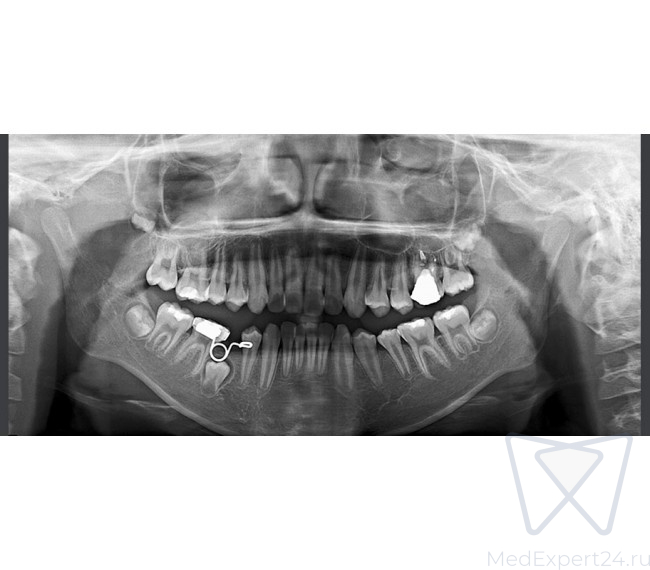

- Четкие изображения с помощью технологии MAR (Metal Artifact Reduction) – алгоритм уменьшения влияния артефактов, возникающих от металлов в челюсти. Уменьшает эффект отражения рентгеновских лучей от объектов с высокой плотностью и позволяет улучшить диагностику вокруг этих объектов.

- Четкие изображения с помощью технологии AMF (Adaptive Moving Focus) – адаптивное смещение фокуса, для получения качественного панорамного снимка и оптимизации соотношения сигнал/шум

- Стандартная панорамная

- Детская панорамная

- Ортозональная панорамная

- Панорамная съемка широкой зубной дуги

- Ортогональная панорамная